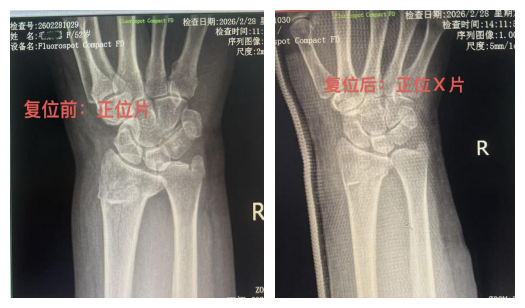

复位前影像显示:桡骨远端骨折端向掌侧明显移位,掌倾角变小,手腕呈现典型“工兵铲样”畸形。

通过患者复位前后影像资料对比,疗效清晰可见:

复位前:骨折端移位显著,关节面塌陷,腕骨排列紊乱;

复位后:骨折端对位、对线良好,关节面恢复平整,腕关节结构回归正常。